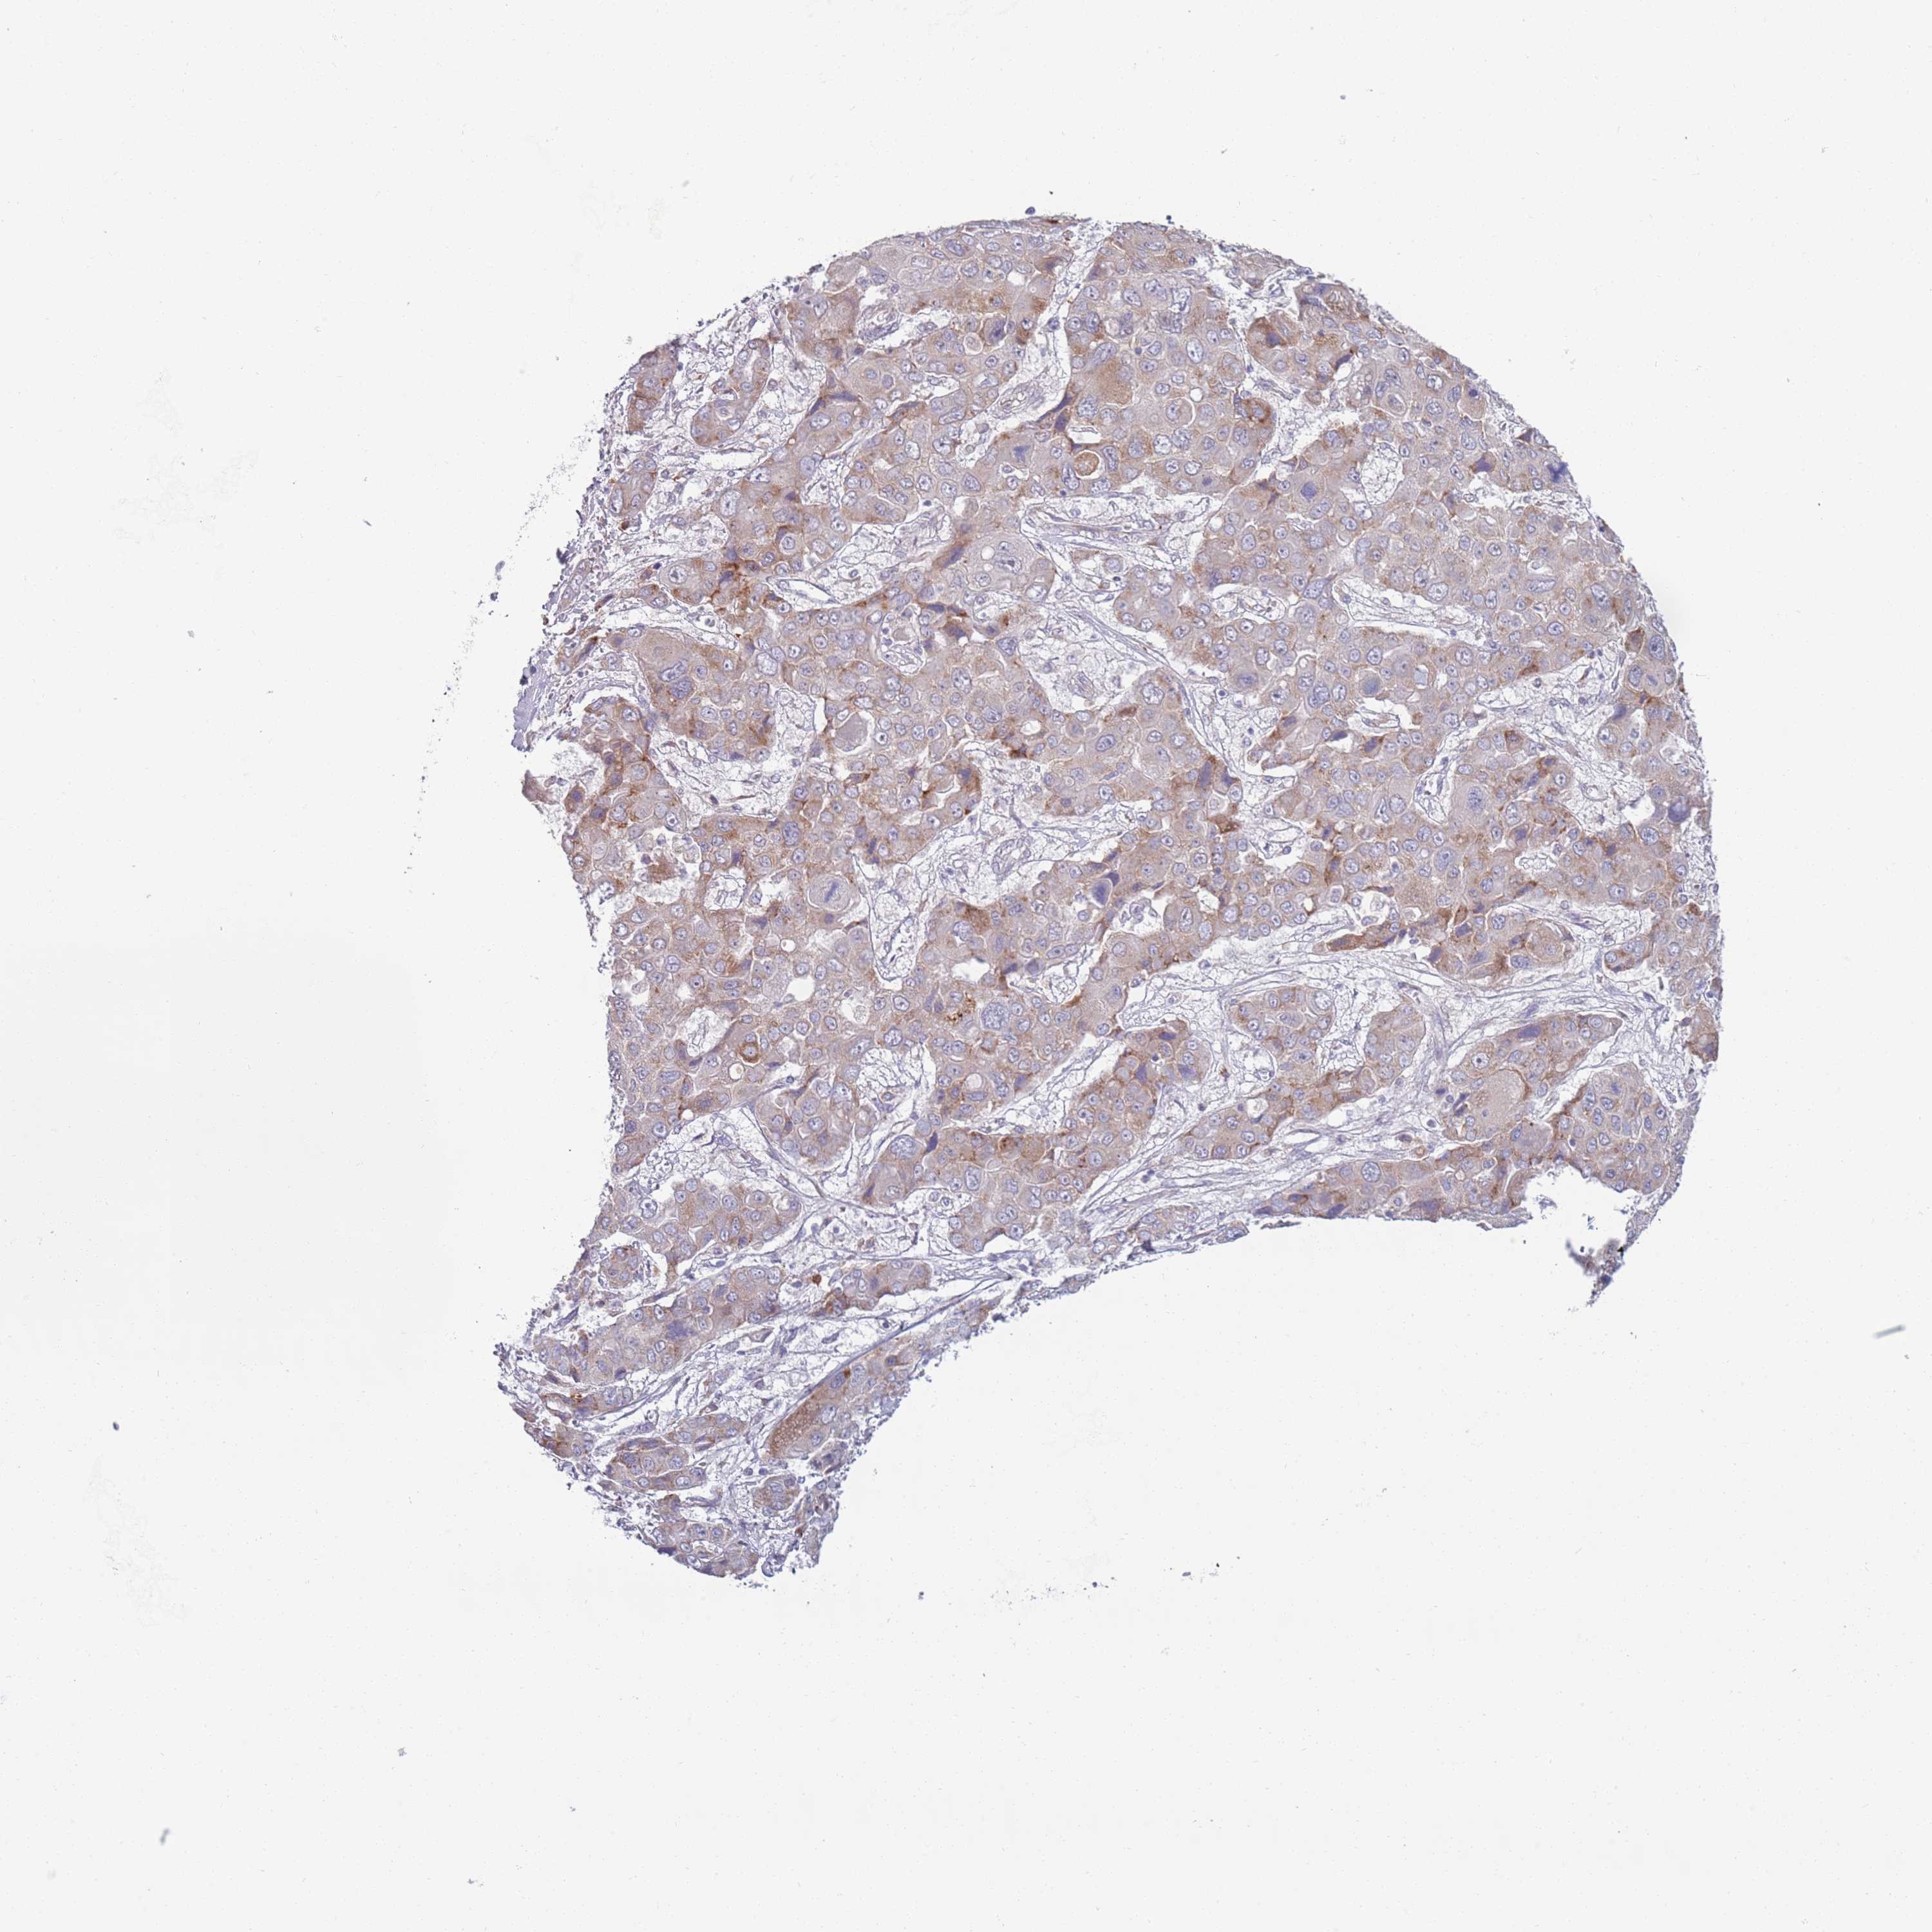

LIVER CANCER - Protein expressioni

A mouse-over function shows sample information and annotation data. Click on an image to view it in a full screen mode. Samples can be filtered based on level of antibody staining by selecting one or several of the following categories: high, medium, low and not detected. The assay and annotation is described here.

Note that samples used for immunohistochemistry by the Human Protein Atlas do not correspond to samples in the TCGA dataset.

Antibody stainingi

Antibody staining in the annotated cell types in the current human tissue is reported as not detected, low, medium, or high, based on conventional immunohistochemistry profiling in selected tissues. This score is based on the combination of the staining intensity and fraction of stained cells.

Each image is clickable and will lead to virtual microscopy that enables deeper exploration of all samples and also displays staining intensity scores, fraction scores and subcellular localization as well as patient and tissue information for each sample.

Antibody HPA048884

Staining

High

Medium

Low

Not detected

Intensity

Strong

Moderate

Weak

Negative

Quantity

>75%

75%-25%

<25%

None

Location

Nuclear

Cytoplasmic/membranous

Cytoplasmic/membranous,nuclear

Cholangiocarcinoma

Carcinoma, Hepatocellular, NOS